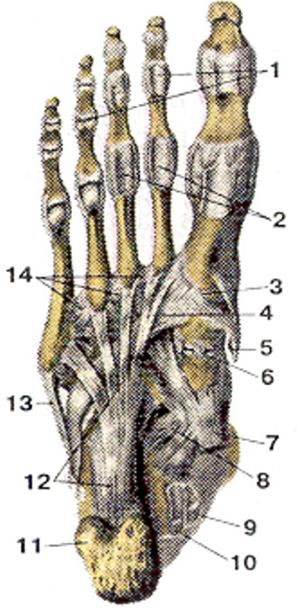

Анатомия суставов Шапарова и Лисфранка: фото и информация